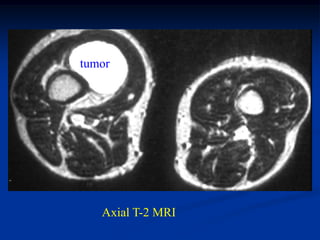

Case #298.1   Hemangioma Ankle                Sag Gad

Case #298.1

15 year male with tender

mass lateral side of forefoot

for many years

Axial T-1

T-2

Sag T-1

Cor T-2

Hemangioma Case #298.1 15 yearmale with tender mass lateral side of forefoot for many years